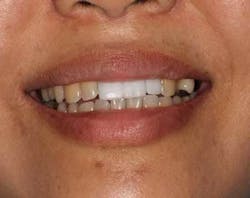

A 43-year-old female with a noncontributory medical history taking no medication and having no known food/drug allergies presented to my general dental office with a chief complaint of having “loose teeth with an underbite.” Clinically, she had generalized, moderate, chronic periodontal disease and was missing teeth Nos. 8 through 10. She had a Class III malocclusion with pathologic flaring of her remaining anterior teeth. She had both vertical and horizontal tissue loss in the No. 8 through 10 region. The patient wore a transitional partial denture to replace the anterior missing teeth that was placed in edge-to-edge occlusion by her previous dentist. (Fig. 1) She did not like having a removable prosthetic and desired a fixed option in the form of implants to replace her missing teeth. I sent her to the periodontist for a periodontal consult for her remaining dentition and dental implants to replace her missing front teeth.